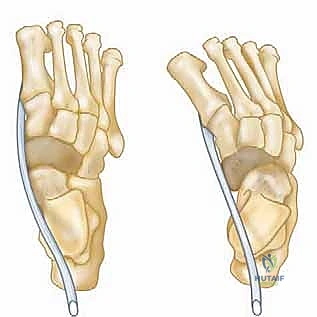

Anterior Tibialis Transfer for Residual Clubfoot Deformity ## DEFINITION The incidence of residual deformity in congenital clubfoot ranges from 26.6% to 50%, regardless of the initial treatment provided. 2The disparity in the reported incidence is due to varying severity of clubfoot deformity, different methods of treatment, and, in part, differing definitions of residual deformity.Residual deformities include isolated equinus, cavus, metatarsus adductus, hindfoot varus, forefoot supination, and combinations of the above.Dynamic forefoot adduction and supination can be observed after clubfoot treatment with or without soft tissue releases.Dynamic forefoot supination deformity results from muscle imbalance. Anatomic imbalances can be due to primary absence or weakness of the anterior tibialis or peroneal muscles or as a result of neurologic abnormalities in the central nervous system or the peroneal nerve. Functional muscle imbalance can result from residual medial displacement of the navicular on the head of the talus. In this case, because its insertion is medially displaced, the anterior tibialis becomes a forefoot supinator instead of a dorsiflexor ( FIG 1). Illustration 1 for Why Anterior Tibialis Muscle Transfer Fixes Clubfoot --- Illustration 2 for Why Anterior Tibialis Muscle Transfer Fixes Clubfoot ### FIG 1 • Normal foot versus supinated foot. Medial subluxation of the navicular, the medial cuneiform, and the first metatarsal results in supination deformity as the line of pull of the tibialis anterior tendon directs the foot into supination instead of dorsiflexion. The aim of treatment is to correct any fixed deformity and to rebalance the muscles of the foot, thereby correcting dynamic deformity and improving foot alignment. ## ANATOMY The anterior tibialis muscle originates from the upper two-thirds of the tibia.The anterior tibialis tendon fibers rotate 90 degrees from the musculotendinous junction to its insertion on the medial cuneiform and first metatarsal.Medial rotation begins proximally, so the most medial muscle fibers proximally rotate to the posterior surface of the tendon near the midpoint and continue to rotate so that their final insertion is as the distal-lateral fibers on the first metatarsal.Meanwhile, the most lateral muscle fibers proximally rotate to the anterior surface at the midpoint andcontinue distally to insert on the cuneiform as the proximal-medial fibers ( FIG 2).4 Illustration 3 for Why Anterior Tibialis Muscle Transfer Fixes Clubfoot --- Illustration 4 for Why Anterior Tibialis Muscle Transfer Fixes Clubfoot ### FIG 2 • Anatomy of the tibialis anterior muscle-tendon. The anterior tibialis tendon fibers rotate 90 degrees from their musculotendinous junction to their insertion on the medial cuneiform and the first metatarsal such that the proximal-medial insertional fibers on the cuneiform begin as the lateral fibers at the musculotendinous junction (see window).

The anterior tibialis muscle is active in two important stages of the gait cycle; it concentrically fires during the initiation of swing phase and keeps the foot dorsiflexed during early swing phase and then it relaxes. The anterior tibialis muscle then fires eccentrically as the foot is lowered to the floor from heel strike to foot flat in stance phase.As a dorsiflexor, the anterior tibialis muscle opposes gravity and the strong gastrocsoleus complex. Importantly, the anterior tibialis muscle may also be a supinator of the forefoot in the face of peroneal longus weakness or medial displacement of the insertion.There are important bony abnormalities associated with residual clubfoot deformity.The subtalar joint may have an absent anterior facet and small, narrow medial and posterior facets, resulting in restricted subtalar motion. In this setting, the calcaneus does not slide fully into valgus with casting such that the navicular remains medially displaced.The navicular itself is wedge-shaped and is medially displaced along with the cuneiforms and metatarsals. 10 With medial displacement of its insertion, the biomechanical advantage favors the action of the anterior tibialismuscle as a strong supinator over its role as a dorsiflexor ( FIG 3). ## PATHOGENESIS The cause of residual clubfoot deformity may be incomplete correction or recurrence of deformity as part of the natural history of the resistant clubfoot.Electromyographic and magnetic resonance imaging (MRI) studies have demonstrated that the peroneal muscle group can be absent, smaller, and relatively weaker, thus increasing the supinator action of the tibialis anterior muscle. 1, 3Medial subluxation of the navicular is considered an important factor influencing both the appearance of the foot and the lateral rotation of the ankle. 9In addition to the bony abnormalities associated with clubfeet, anatomic variations from the customary insertion of the anterior tibialis muscle into adjacent areas of the first metatarsal and medial cuneiform occur in 10% of pathologic specimens.In these variants, the distal anterior tibialis muscle inserts more medially than normal, optimizing the force vector for supination. 8 Illustration 5 for Why Anterior Tibialis Muscle Transfer Fixes Clubfoot --- FIG 3 • Bony abnormalities associated with residual clubfoot deformity. The navicular is wedge-shaped and is medially displaced along with the cuneiforms and metatarsals. Illustration 6 for Why Anterior Tibialis Muscle Transfer Fixes Clubfoot --- * FIG 4 • Hindfoot varus. When untreated, residual deformity may become stiff. When fixed inversion deformity is combined with residual equinus deformity, hindfoot varus occurs. *